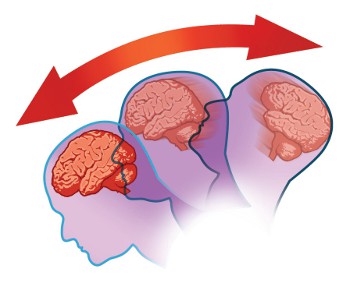

A concussion is the most common type of closed brain injury and is classified as a mild traumatic brain injury (mTBI). Concussions occur when a blow, bump, or sudden movement causes the brain to move rapidly inside the skull, temporarily affecting how the brain functions.

Repeated concussions can increase the risk of long-term challenges, including:

Research has shown that individuals exposed to repeated head impacts, such as athletes in sports like boxing, football, and hockey, may experience higher rates of cognitive and emotional health challenges later in life.